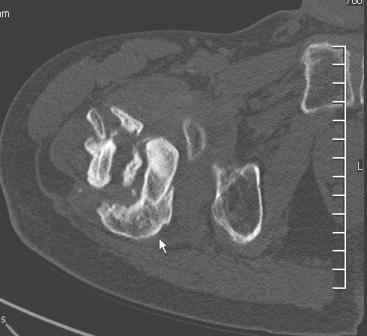

Сросшийся со смещением чрез-подвертельный перелом

Больной Н. 44 года травма 1,5 года назад июнь 2008 года чрез-под вертельный перелом правого бедра. Во время лечения у больного развился алк. делирий, проводилось консервативное лечение перелома.

Осмотрен 30.10.09.

Беспокоят боли, укорочение конечности. Укорочение 3 см. Ногу поднимает, сгибание ограничено, ротационные движения в полном объеме. На КТ перелом сросся за счет костной мозоли. Что делать?

Протез? Если «да» Можно ли обойтись стандартной ножкой Corail?

Или межвертельная остеотомия?